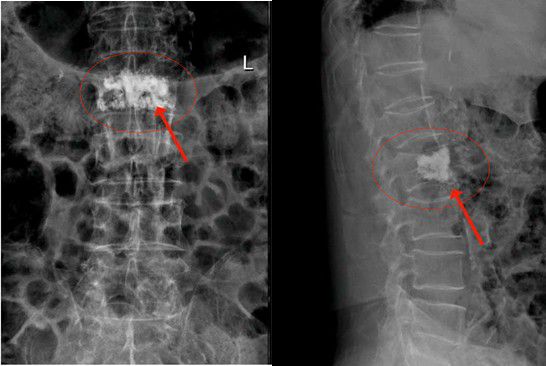

2月3日陳大伯由家人送到我院治療,收入外四科(骨科)。經腰椎MR檢查,發現腰椎第二椎體(L2)壓縮性骨折,椎體中間前緣壓縮變空。高齡患者如果采用保守治療,往往骨折遷延難愈,需要卧床至少1個月以上。老年人基礎疾病多,如陳大伯就患有高血壓、糖尿病、陳舊性心肌梗死等疾病,長期卧床容易誘發各類并發症而危急生命。而傳統開放性手術創傷大,高齡患者難以承受。這也是以往老年人最怕骨折的原因。

△腰椎第二椎體(L2)壓縮性骨折